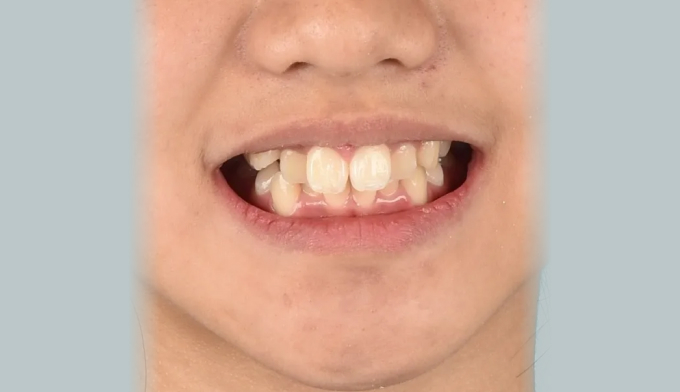

위턱, 아래턱 모두 치아 배열 공간이 부족한 경우 입니다.

확장장치를 이용해 공간 부족을 해결하고 치열을 배열하면 간단히 끝낼 수 있습니다.

이때 입술의 두께나 위치, 위아래 앞니의 각도를 종합적으로 고려하여야 합니다.

치아를 배열한다고 앞니가 뻐드러지면 잘못된 교정치료입니다.

총 치료기간은 20개월 소요되었습니다.